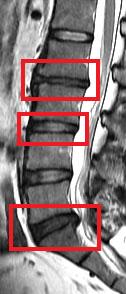

Low back pain affects every population worldwide, and is a leading cause of ill-health and sick leave in the working population of Hong Kong. One of the major causes of low back pain is degeneration of the joints of the spine, known as the intervertebral discs. A cohort study conducted by the Department of Orthopaedics & Traumatology at The University of Hong Kong Li Ka Shing Faculty of Medicine reveals that being obese in adulthood doubles the likelihood of having disc degeneration and developing more severe forms of the condition than those of normal weight. These findings are of public health concern and were published in the latest issue of the authoritative journal Arthritis and Rheumatism.

The current study was a cross-sectional assessment of adults from this cohort who were 21 years of age and older. A total of 2,599 individuals were assessed with magnetic resonance imaging (MRI). Amongst them, 27% (n=709) did not have disc degeneration while 73% (n=1,890) had. Of the subjects who have disc degeneration, 7% were underweight, 48% were in the normal weight range, 36% were overweight, and 9% were obese. Overweight and obese individuals were also found to have a greater extent and severity of disc degeneration in comparison to those individuals of normal weight or underweight.